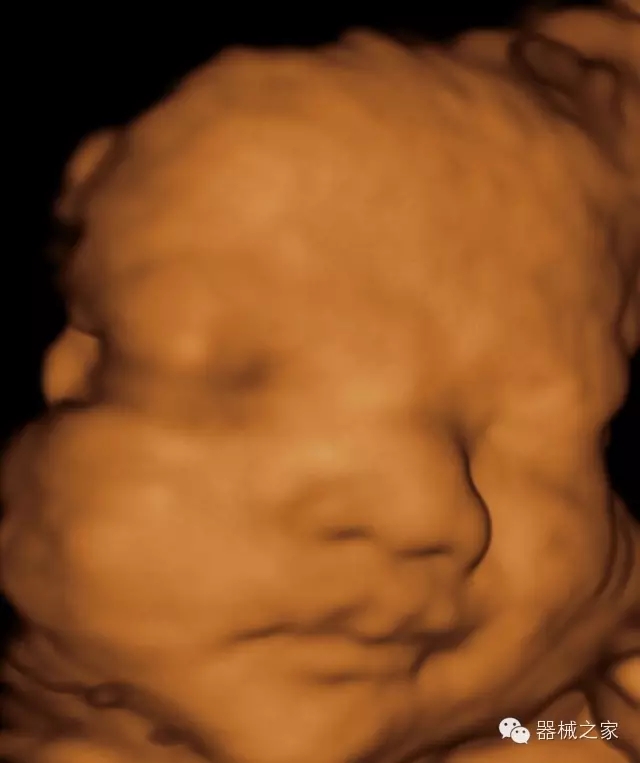

臨床圖片賞析

·完整的3D/4D臨床應(yīng)用,STIC, MCUT 和Auto NT等滿足產(chǎn)科所有應(yīng)用;

·更高的HQ羊膜腔鏡成像技術(shù)精細(xì)觀察每一個(gè)暗區(qū)細(xì)節(jié);

·高效3D/4D成像技術(shù):高速的4D幀頻,豐富的3D成像模式,智能斷層切片功能;